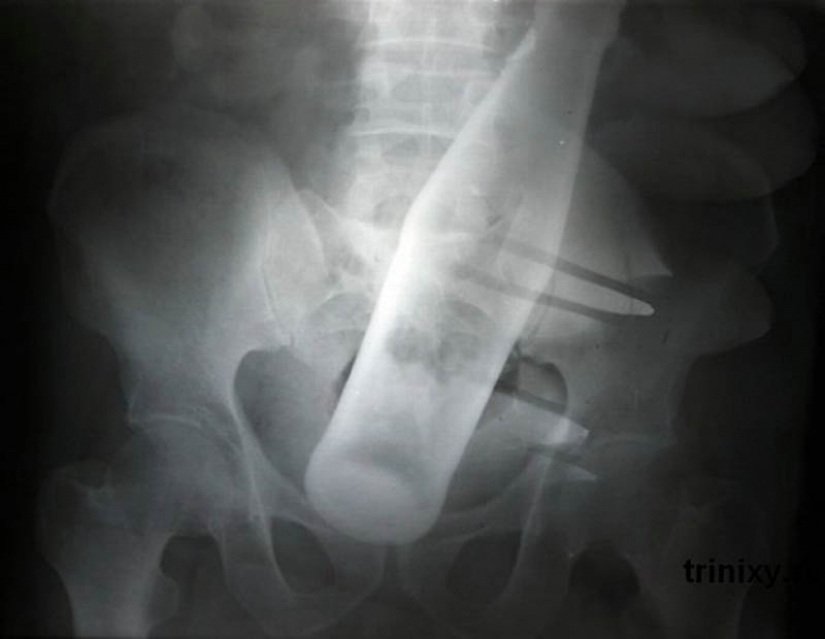

20. Bottle of "Pepsi" in the anus 60-year-old man.